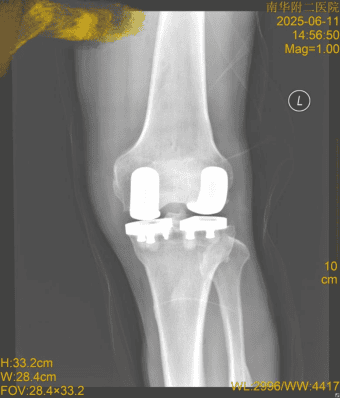

近日,南华大学附属第二医院关节与运动医学科成功为一名67岁膝关节骨性关节炎患者实施同期双侧单髁置换术。该手术由科室主任谭光华教授领衔团队完成,标志着医院在保膝治疗领域取得重要技术突破。

患者周先生因左膝关节反复疼痛并加重入院,确诊为骨性关节炎,主要累及内侧间室,外侧间室也有明显退变。针对其年龄适中、活动需求高且前交叉韧带完好的特点,谭光华教授团队决定采用技术要求极高的同期双单髁置换术。

谭光华教授介绍,相比传统全膝关节置换,双单髁置换术具有三大核心优势:最大程度保留患者自身骨量及韧带结构、手术创伤小、康复速度快(患者术后次日即可下地活动)。手术采用髌旁内侧入路,精准完成内外侧关节面截骨,并特别注重保留前后交叉韧带以维持关节稳定。整台手术仅耗时1小时10分钟,出血量约180ml。患者术后第2天即开始康复锻炼,第5天顺利出院。术后3周随访显示,其膝关节功能(HSS评分)已从术前的52分显著提升至86分。